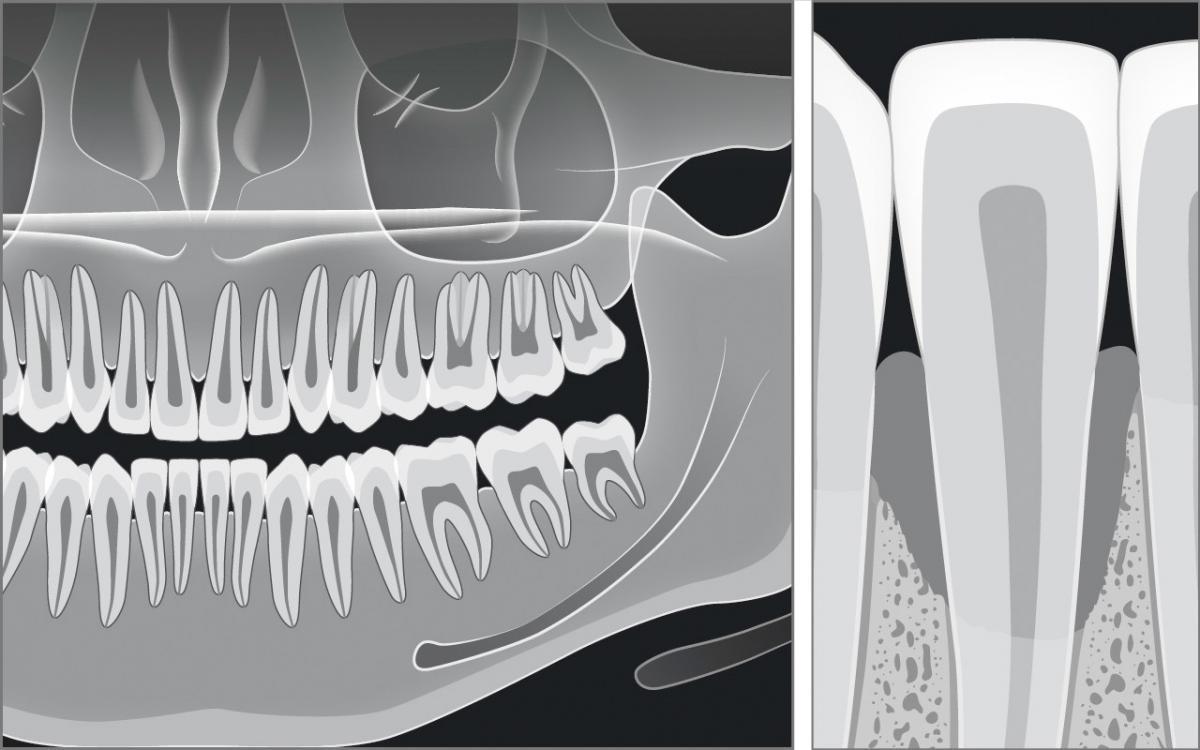

Röntgenbefund

Die Messungen mit der Zahnfleischsonde können Stellen im Gebiss mit erhöhten Sondierungstiefen aufzeigen, die mit einem Röntgenbefund zusätzlich beurteilt werden müssen.

Ein Röntgenbefund besteht im einfachsten Fall aus zwei Bildern (Bissflügelaufnahmen) und im umfangreichsten Fall aus einem sogenannten Röntgenstatus mit zusätzlich bis zu 14 Röntgenbildern oder einem Orthopantomogramm. Die angefertigten Röntgenbilder müssen den zahnumgebenden Kieferknochen darstellen und es so ermöglichen, den Schweregrad des Knochenabbaus einzuschätzen.

In jedem Röntgenbild aus der Zahnarztpraxis muss das Gebiss sowohl auf Karies als auch auf Parodontitis hin geprüft werden.